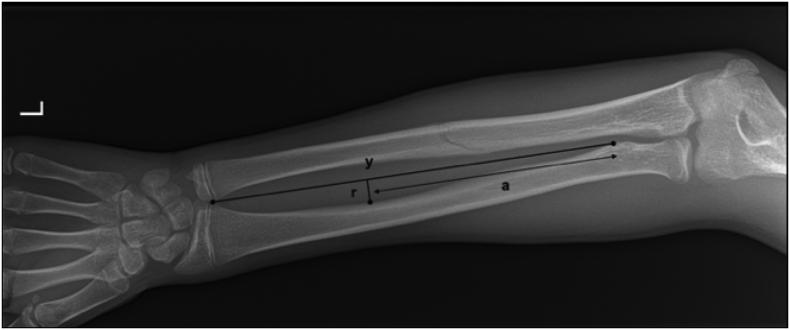

A 13-year old male sustained a diaphyseal fracture of the left ulna after a fall on the outstretched hand which was treated conservatively. A non-impact incident (push up on outstretched arm) 4.5 months after the initial trauma caused an ulnar fracture at the same location and was initially considered a simple refracture. Operative treatment was decided on due to significant clinical forearm valgus alignment. Intraoperatively however, a mobile non-union of the ulna was found and anatomic reduction was not possible due to radial bowing. Exploration of the radius showed a clear malalignment with periosteal callus reaction, indicative of a mal-union of the radial bone as a result of the initial injury. To correctly restore alignment, a closing wedge osteotomy of the radius was necessitated followed by plate and screw fixation of both the radius and the ulna.

In this patient, failure of recognizing the associated plastic deformity of the radius during the initial presentation led to radial malunion and non-union of the ulna. As a result of this complication, an osteotomy was necessary which probably could have been prevented if an adequate initial diagnosis had been made.